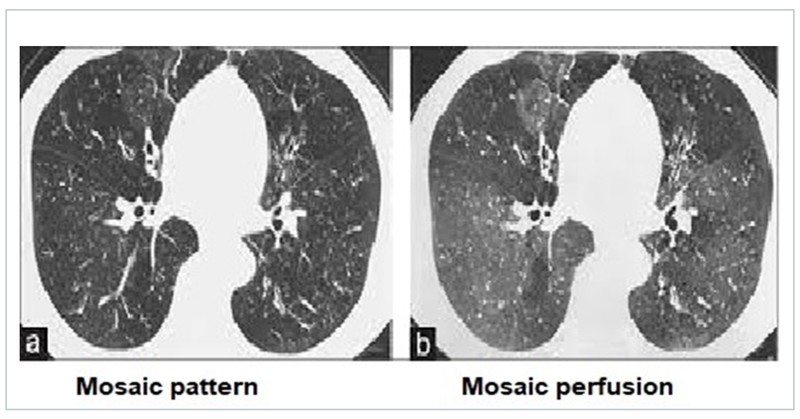

Mosaic attenuation/pattern and mosaic perfusion

Mosaic attenuation is defined as heterogeneous areas of differing lung attenuation. This is the result of diverse causes that include diseases of the small airways, pulmonary vasculature, alveoli, and interstitium, alone or in combination. Mosaic perfusion is the exaggeration of the mosaic attenuation pattern on expiratory scans. It represents air trapping and small airway disease which could be due to obliterative bronchiolitis (OB), COPD, asthma, and interstitial lung diseases (ILD) like hypersensitivity pneumonitis.